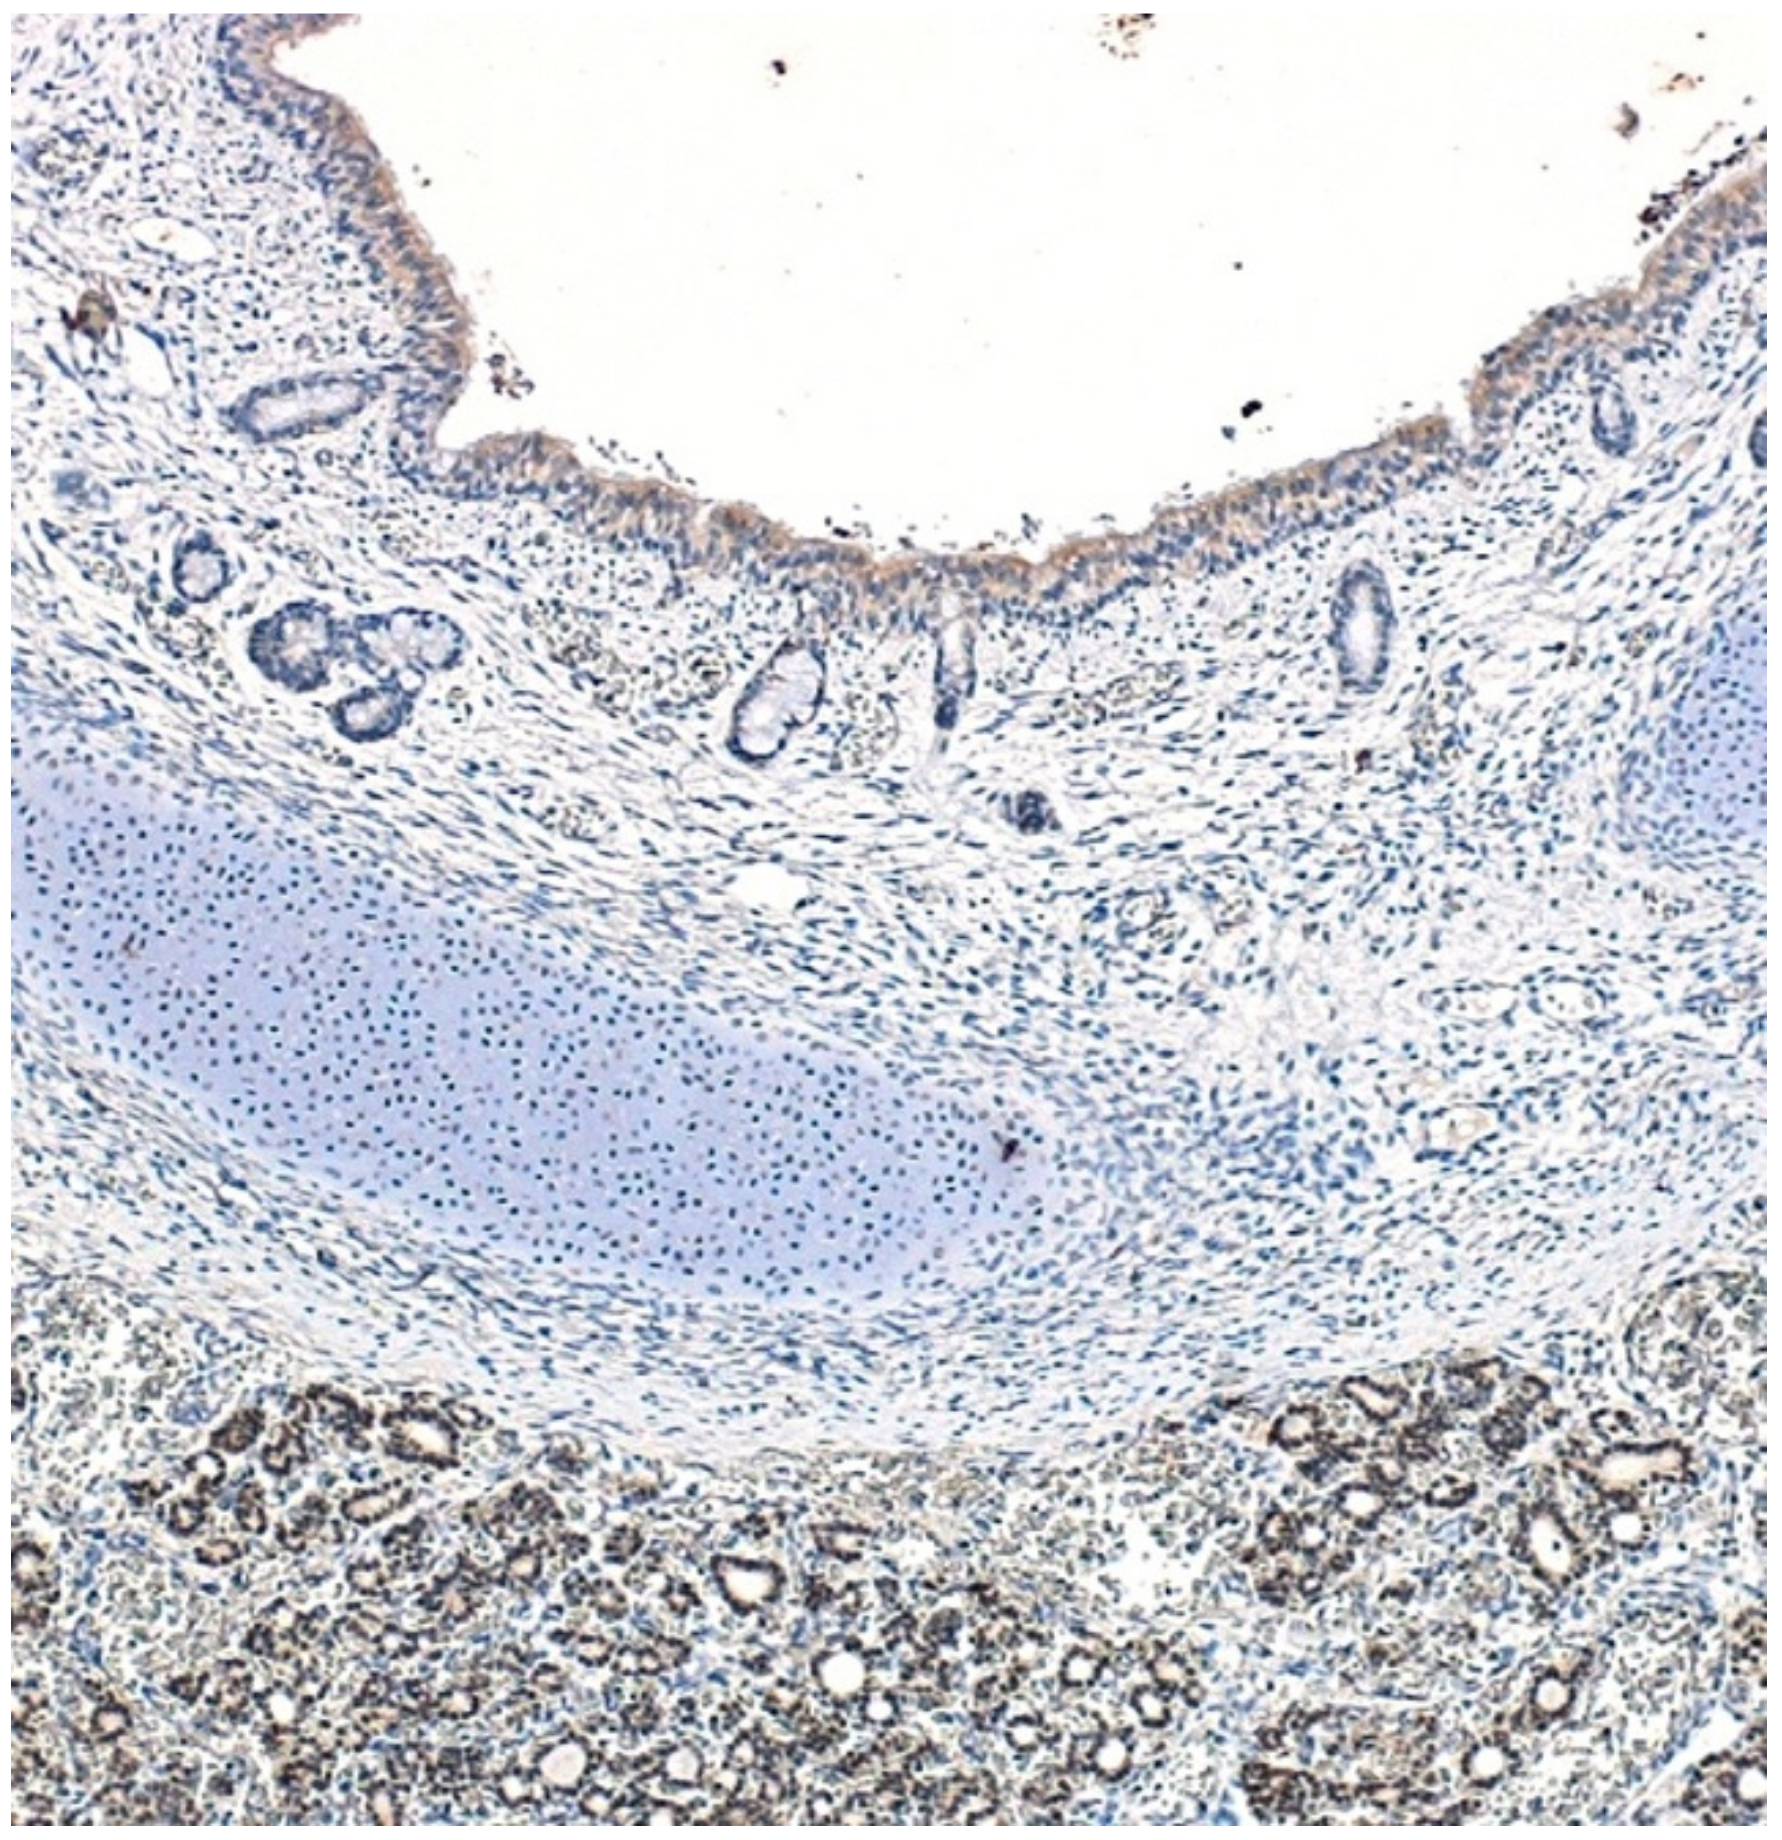

3.1. Fetuses

- Stahlman, M.T.; Gray, M.E.; Whitsett, J.A. Expression of thyroid transcription factor-1(TTF-1) in fetal and neonatal human lung. J. Histochem. Cytochem. 1996, 44, 673–678. [Google Scholar] [CrossRef]